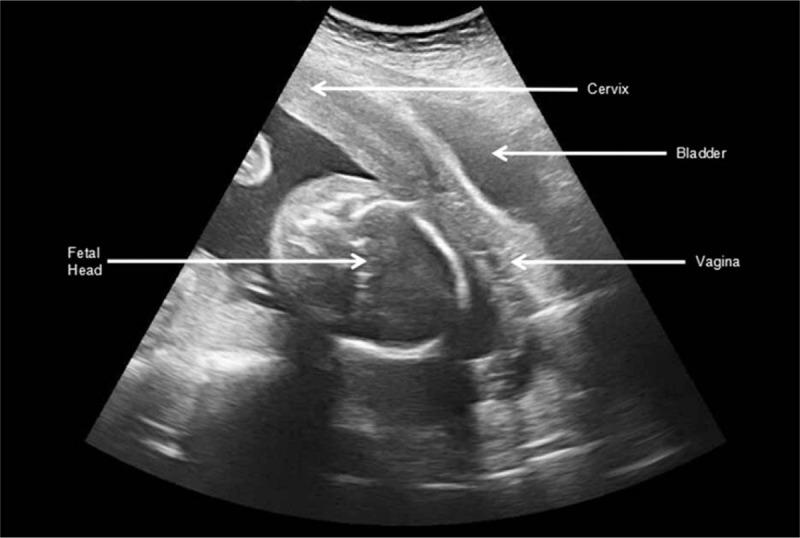

A diagnosis of fibroid degeneration was made through ultrasound and magnetic resonance imaging. The patient was hospitalized with conservative treatment. An abdominal myomectomy was performed at 22 weeks' gestation because her condition had deteriorated. Incarcerated uterus was not suspected even at the time of myomectomy. But within 24 hours after myomectomy, diagnosis of incarcerated gravid uterus was made by ultrasound.

Incarcerated gravid uterus was found spontaneously reduced three weeks after myomectomy by ultrasound. A transverse Cesarean incision was performed at 32 weeks' gestation. A male infant weighing 2120 g was delivered with Apgar scores of 10 and 10 at 1 and 5 minutes, respectively. Postoperative course was uneventful.